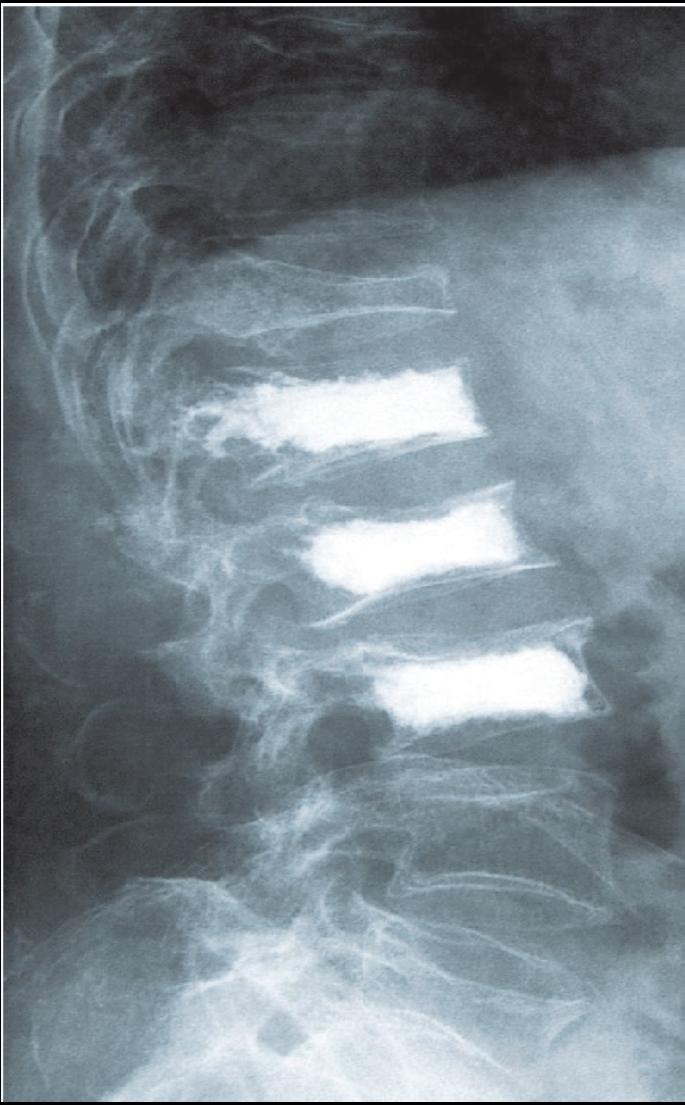

Eines der Geschäftsfelder der InnoTERE GmbH wird die Herstellung von bioaktivem Knochenzement zur Behandlung und Aussteifung ostheoporotischer Knochen sein.

Hier am Beispiel der Wirbelsäule.Die InnoTERE BioMaterials GmbH - Innovation für Tissue Engineering und Regeneration - stellte deren Geschäftsführer, Herr Dr. Berthold Nies, vor. Das Unternehmen wurde 2004 gegründet und ist seit Herbst im BioZ Dresden ansässig. Der Standort Dresden wurde wegen der Nähe zu den wichtigsten wissenschaftlichen Partnern, wie dem Max-Bergmann- Zentrum, gewählt. In einem gut illustrierten Vortrag zeigte Dr. Nies, welche Forschungsleistungen auf dem Gebiet der regenerativen Medizin zur Knochenregeneration, für das Verankern von Knochenimplantaten und zur Behandlung von Knochenschäden durch sein Unternehmen erbracht wurden und werden. Die InnoTERE GmbH ist einer der 10 Sieger des vom BMBF ausgeschriebenen Wettbewerbs für Medizintechnik 2005. Nach ihren Vorträgen beantworteten die Referenten zahlreiche Fragen aus dem Auditorium.